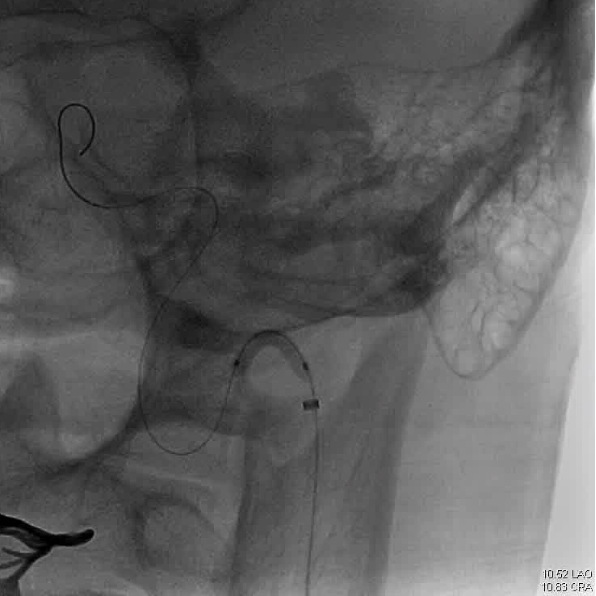

DSA显示ICAO

微导管造影证实MCAO

手术过程

中间导管配合在长鞘和小球囊的配合下穿过迂曲夹层的颈内动脉。

微导管微导丝越过MCA闭塞段,置入取栓支架支架。

微导管微导丝穿过夹层段,4.0×20mm球囊再次反复贴附夹层段,促进内膜贴壁。

造影观察,管腔狭窄较前好转,血流状态稳定,结束手术。

2018-3-9 日复查CT及CTA,夹层自愈过程中,无栓塞,转康复科行康复训练。